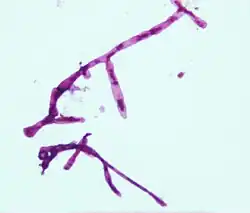

Nejrychlejší metodou je mikroskopie granul získaných z hnisu. Tato metoda využívá 10% KOH ke štěpení hlenu a keratinu. V barveném preparátu roztlaku granul jsou hledány hyfy a spory. Metoda však nemá dostatečnou specifitu a sama k diagnostice nestačí.[18]